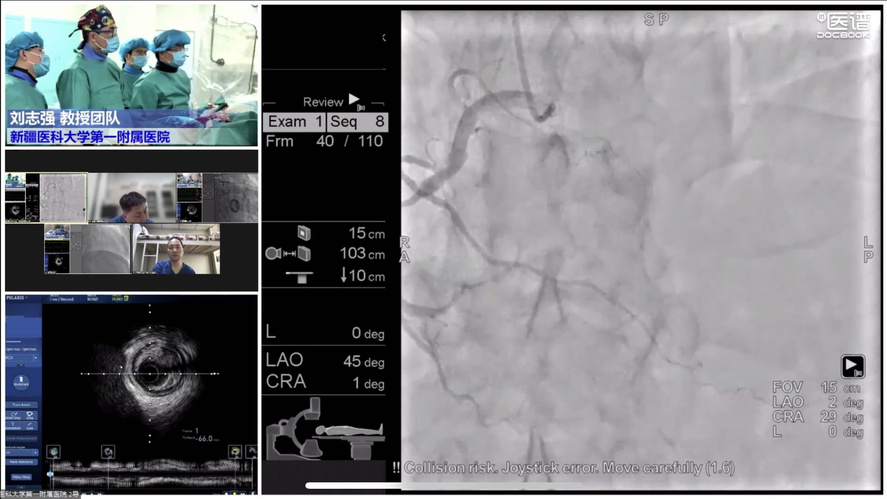

COE卓越中心成立旨在实现头部、地市、县域各医疗中心的联动,实现远程会诊与指导交流。疫情虽然隔绝各地区线下交流,但技术持续发展,远程需求快速增长,必将成为未来发展大趋势。其次希望通过COE中心将多年发展的影像数据进行收集整理发掘更多价值。第三是标准化培训体系建立,既可开展线上远程教学又可在疫情缓解时线下手把手教学,实现上下实时互动。波士顿科学始终对国内影像学与功能学技术的发展充满信心,也希望在波科本土化的进程中,与中国专家共同促进技术创新,服务广大中国患者。会议期间,四川大学华西医院、西安交通大学第一附属医院、南方医科大学南方医院、新疆医科大学第一附属医院、宁夏医科大学总医院心脑血管病医院联袂呈现17例高质量手术直播,所有与会专家各抒己见,畅谈影像技术实战应用。其中四川大学华西医院何森教授带来IVUS指导下LAD重度狭窄伴钙化手术一例。陈勇教授演示一例IVUS指导下的多支血管病变手术;周名纲教授演示一例一月内二次处理的多支病变复杂手术。王勉教授演示一例IVUS指导下逆向开通LAD慢性次全闭塞手术;黄宝涛教授带来了一例IVUS指导下旋磨处理LAD严重钙化病变;李晨教授演示了一例IVSU指导下开通无残端CTO病变的病例。西安交通大学第一附属医院郭宁、张勇教授团队带来造影剂过敏患者PCI治疗,通过IVUS不仅明确病变部位的斑块性质及血管解剖情况,同时确定支架落脚点位置及支架选择。最后在IVUS指导下顺利植入三枚支架,充分展示IVUS对指导低造影剂PCI的临床价值。由南方医科大学南方医院修建成、韩渊、梁鸿彬教授团队带来IVUS指导前降支CTO无残端的病例则先后在对角支、间隔支行IVUS找到前降支开口残端,同时IVUS显示,前降支开口后走行与间隔支夹角较小,近乎平行走行。明确解剖特点后果断决定逆向策略,最终在IVUS指导下,逆向导丝成功进入前降至病变部位远端建立导丝轨道,手术迎来完美结果。宁夏医科大学总医院心脑血管病医院仇玉民、胡光欣教授带来一例右冠CTO病例,残端似乎存在微通道,本计划行ADR,首次尝试正向开通时选择波士顿科学Sentai导丝家族Fighter导丝,仇教授提到该款导丝操控性极佳,头端硬度1.5g,外径0.09"直接通过微通道越过病变部位到达右冠远端,成功建立轨道。正确选择导丝取得开门红后,在IVUS指导下顺利植入一枚支架,迅速完成了这例颇具挑战的手术。精彩的手术演示不仅深度传递腔内影像学与功能学指导下优化PCI治疗的理念,更详细阐述IVUS的规范操作和读图技巧,在理论与实践两方面,实现知行合一。